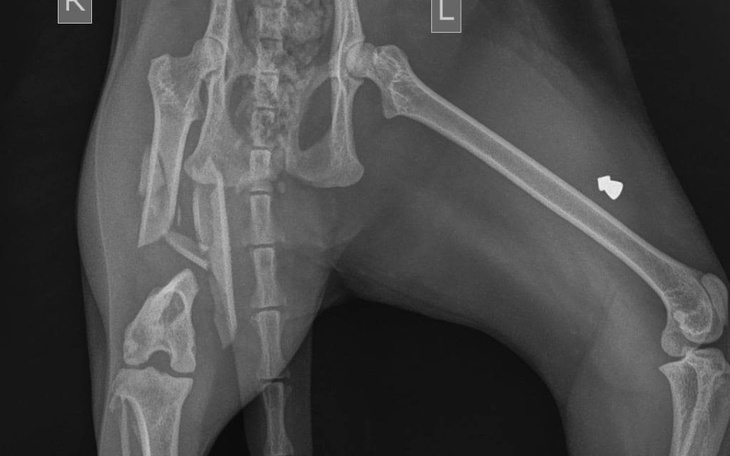

"Misie zabrałam z ulicy gdy miała zaledwie 4 miesiące, a obecnie ma 6 lat. Kilka dni temu wymknęła się z domu, została znaleziona leżąca przy drodze. Zdjęcia RTG wykazały, że jej prawa tylna łapa ma wieloodłamowe złamanie prawej kości udowej z przemieszczeniem odłamów kostnych. Aby uniknąć amputacji potrzebna jest operacja. Pomimo tego, że jest już dorosłym kotem wciąż uwielbia biegać i się bawić, a amputacja łapki byłaby dla niej jak wyrok."